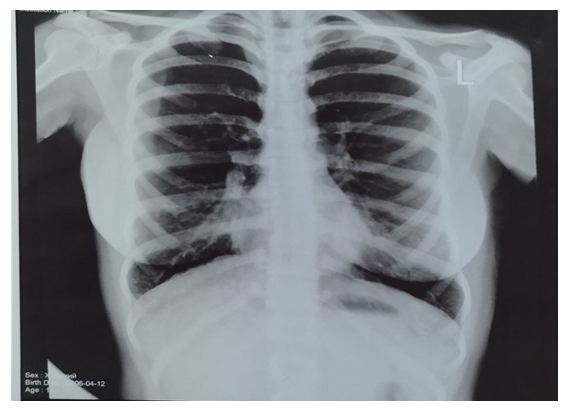

| Figure 2. Patient M.M. is 30 years old. The radiograph shows increased lung volume and deformation in both lung fields, mainly in the lower sections. The coarse and uneven appearance of the bronchovascular pattern indicates a chronic inflammatory process in the bronchial walls |